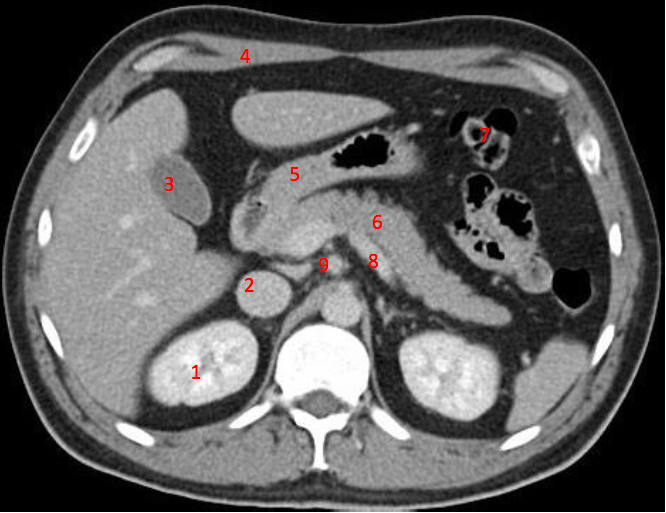

1

Number 3?

IVC

2

Number 1?

R Kidney

3

5

4

A

How well did you know this?

Not at all